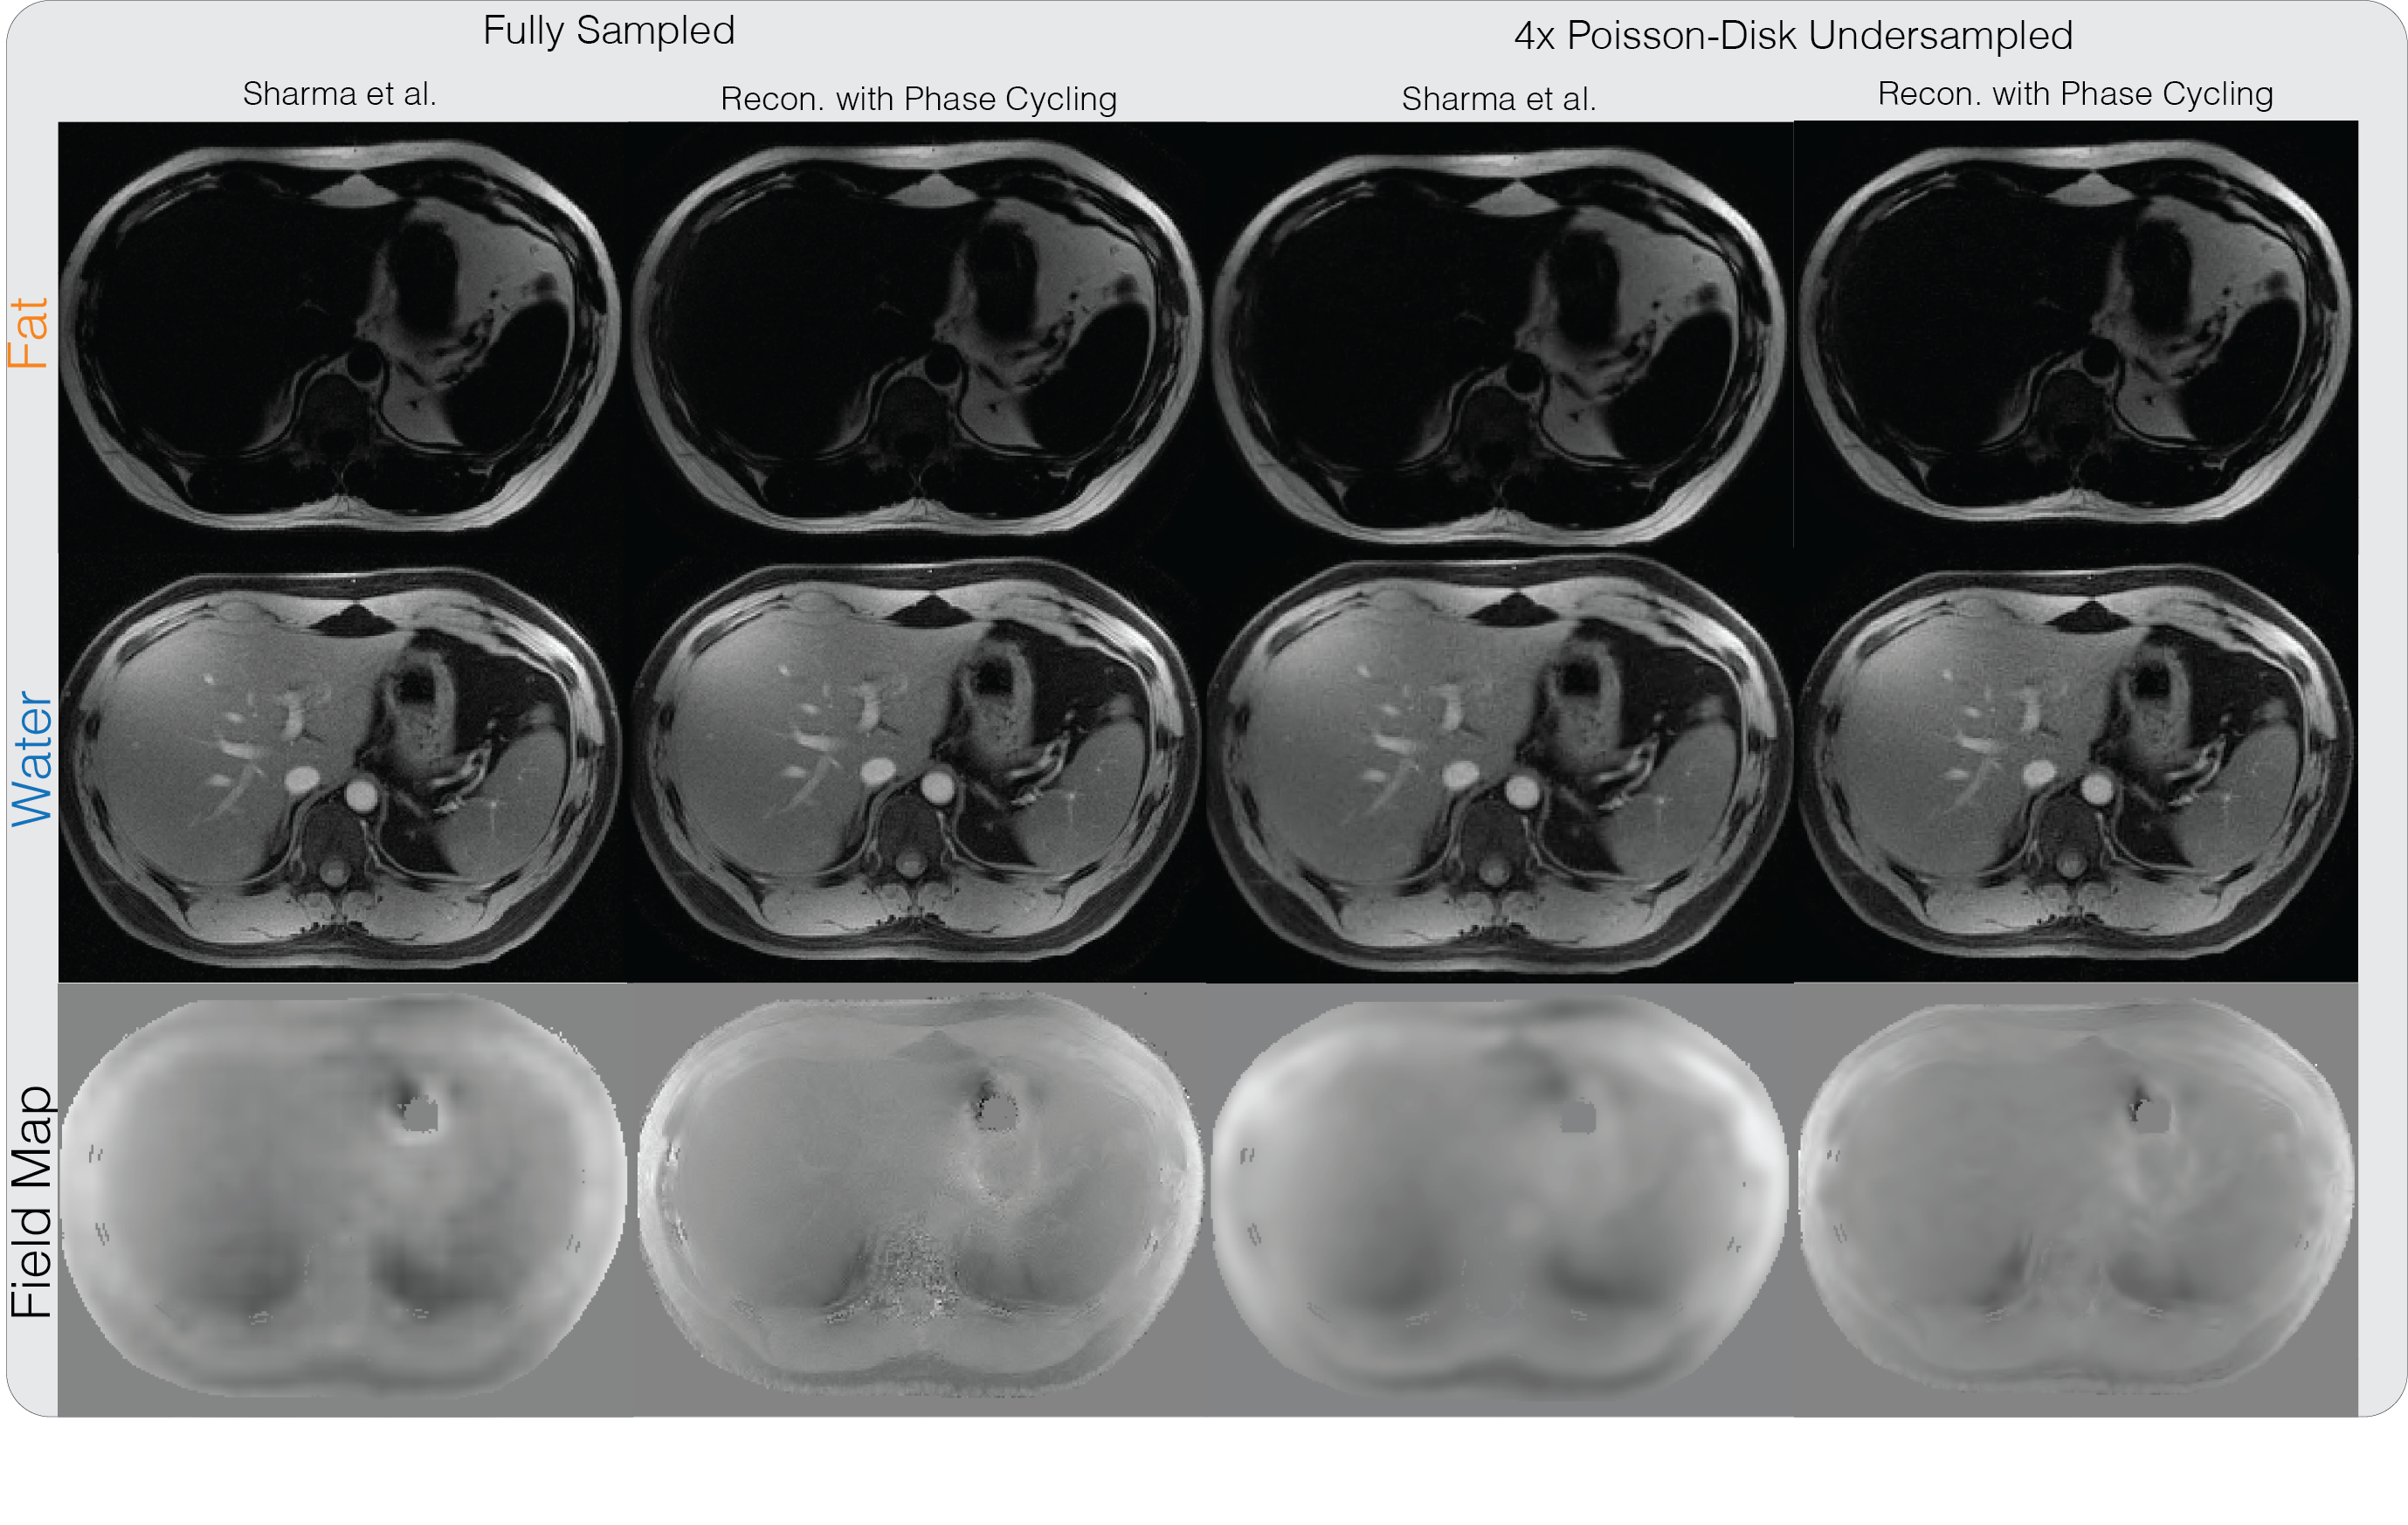

Fully sampled water-fat datasets were obtained from the ISMRM Water-Fat workshop toolbox (available online at http://www.ismrm.org/workshops/FatWater12/data.htm). In particular, an axial slice of the liver with 8-channel coil array dataset was used, which also appeared in the paper of Sharma et al. [9]. The dataset was acquired on a 3T Signa EXCITE HDx system (GE Healthcare, Waukesha, WI), using a GE-investigational IDEAL 3D spoiled-gradient-echo sequence at three TE points with ms, kHz, flip angle of degrees and a sampling matrix. Image masks for displaying the phase images were created by thresholding the bottom 10% of the root-sum-of-squared of the magnitude images.

The liver dataset was retrospectively under-sampled by 4 with a variable density Poisson-Disk sampling pattern. Our proposed method was applied and compared with algorithm of Sharma et al. [9] both for the fully-sampled and under-sampled datasets. The implementation in the Water-Fat workshop toolbox was used with modification to impose the same wavelet transforms as the proposed method, and the default parameters were used.

Supporting Figure S2 shows the water-fat reconstruction results on the liver dataset, combined with PI and CS for the under-sampled case. For the fully sampled case, the water and fat images from the proposed method with phase cycling are comparable with the state-of-the-art water-fat reconstruction result using the method of Sharma et al. [9]. Reconstruction from under-sampled data with the proposed method also results in similar image quality as the fully-sampled data and is consistent with the result shown in Sharma et al. [9]. One instance of our Matlab implementation of the proposed method took 8 minutes and 27 seconds.

S2

Water-fat + PI + CS reconstruction result on a liver dataset with three echoes. Both the method from Sharma et al. and our proposed method produce similar water and fat images on the fully-sampled dataset and the retrospectively undersampled dataset.